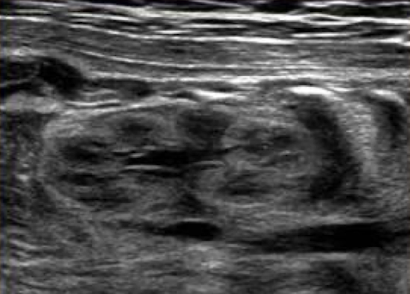

what plane was this taken in?

longitudinal